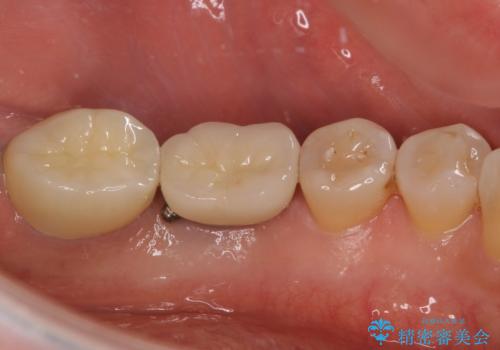

仮歯に変えた時点でしみる症状はなくなり、オールセラミッククラウンはまるで自分自身の歯のような舌触りとなり、大変満足していただきました。